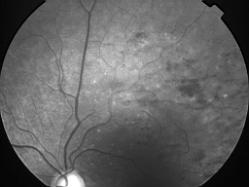

OCCLUSION DE BRANCHE DE LA VTS DE FORME ISCHEMIQUE MAJEURE